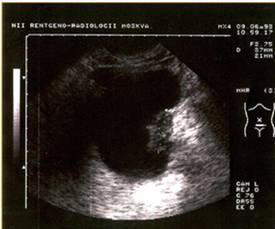

При плановом обследовании больных УЗИ является ведущим методом диагностики опухолей мочевого пузыря. Ультразвуковое сканирование следует проводить только при наполненном мочевом пузыре. Метод позволяет получить документальную информацию о локализации и размерах опухоли мочевого пузыря, одновременно выявить доброкачественную гиперплазию предстательной железы у мужчин пожилого и старческого возраста.

Диагноз опухоли мочевого пузыря только по данным УЗИ может быть установлен у 82% больных. Для более точной диагностики следует выполнять ультразвуковое сканирование при трансабдоминальном и трансректальном расположении датчика. Трансректальное сканирование улучшает визуализацию верхушки и шейки мочевого пузыря, позволяет оценить состояние соседних органов.

Внедрение в клиническую практику ультразвукового исследования не только значительно облегчило диагностику опухолей мочевого пузыря, но и позволило изучать состояние зон регионарного метастазирования. Ультразвуковой мониторинг забрюшинных и внутритазовых лимфатических узлов при раке мочевого пузыря необходим для выбора оптимального метода лечения.